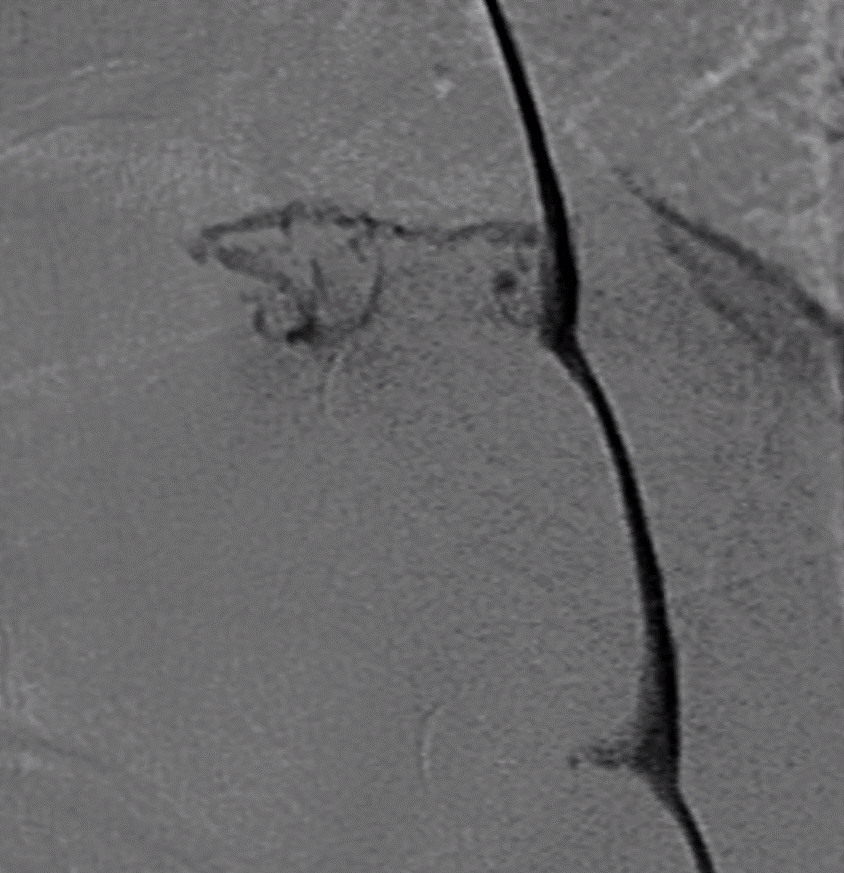

Excited to announce that application for our Skull Base and Pituitary Surgery Fellowship is now open.